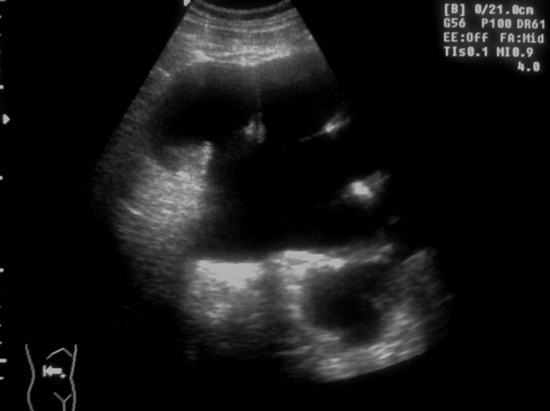

Ещё картинки гидронефроза у ребёнка 6 - ти месяцев, спутать такой гидронефрозище с синусной кистой сложно, а вот с кистой брюшной полости - запросто